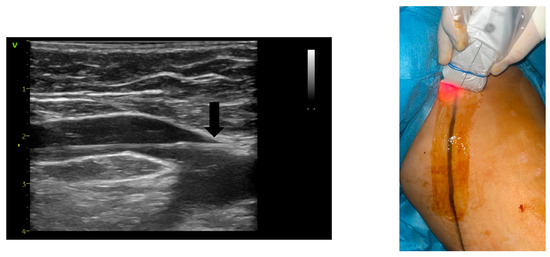

Assessing Endovenous Heat-Induced Thrombosis in Flush Endovenous Laser Ablation: A Study on Incidence, Risk Factors, and Patient Outcomes

J. Clin. Med. 2025, 14(17), 6165; https://doi.org/10.3390/jcm14176165 - 31 Aug 2025

Introduction: The introduction of radial-firing laser fibers has minimized catheter-to-vein distance during endovenous laser ablation (EVLA) for the great saphenous vein (GSV) and anterior saphenous veins (ASVs). This study investigates flush endovenous laser ablation (fEVLA) effectiveness in addressing chronic superficial venous insufficiency (CVI). [...] Read more.

Introduction: The introduction of radial-firing laser fibers has minimized catheter-to-vein distance during endovenous laser ablation (EVLA) for the great saphenous vein (GSV) and anterior saphenous veins (ASVs). This study investigates flush endovenous laser ablation (fEVLA) effectiveness in addressing chronic superficial venous insufficiency (CVI). Materials and methods: This single-center retrospective study analyzed consecutive fEVLA cases with duplex ultrasound follow-up at 1, 4, and 12 weeks. The primary endpoint was clinically significant endovenous heat-induced thrombosis (classes III–IV). Results: Three hundred and twelve patients were recruited (405 affected limbs, 369 GSV, and 36 ASV). CEAP classifications were stratified as follows: C2 in 6.1%, C3 in 34.2%, C4 in 44%, C5 in 2.7%, and C6 in 12.7% of cases. Perforator ligation, phlebectomy, or foam sclerotherapy were carried out in conjunction with EVLA. fEVLA was feasible in all cases. The success rate was 96.78%, defined as EHIT classes 1 and 2, and assessed by ultrasound one week postoperatively. Clinically significant EHIT (2.5% class 3 and 0.2% class 4) was managed with 15 mg rivaroxaban twice daily for 21 days. Follow-up at 4 weeks revealed complete resolution of all EHIT 3–4 cases. No cases of pulmonary embolism or deep vein thrombosis were observed during the study or follow-up period. Conclusions: fEVLA is a safe treatment for superficial CVI across various CEAP classes, and with prompt detection, the minimal complication rate can be completely resolved. Full article

Show Figures

Figure 1